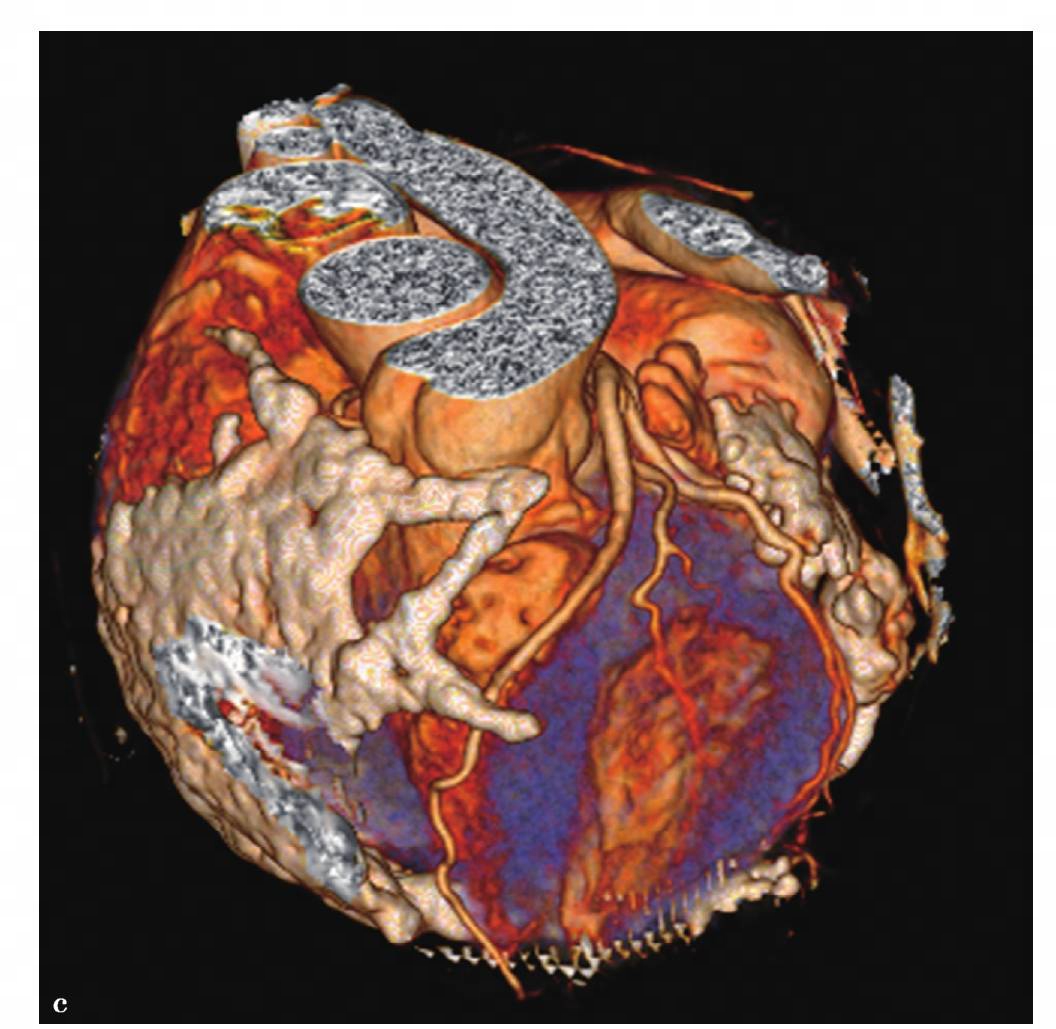

图4 c,心脏CT容积再现图像示冠状动脉未见明显狭窄征象

图6 c,心脏VR重组图像,两者均显示:心包广泛增厚呈壳状钙化,即盔甲心,以右心缘及心膈面为主,主要累及右心房、室,右心房高度扩张,右心室舒张受限而相对较小